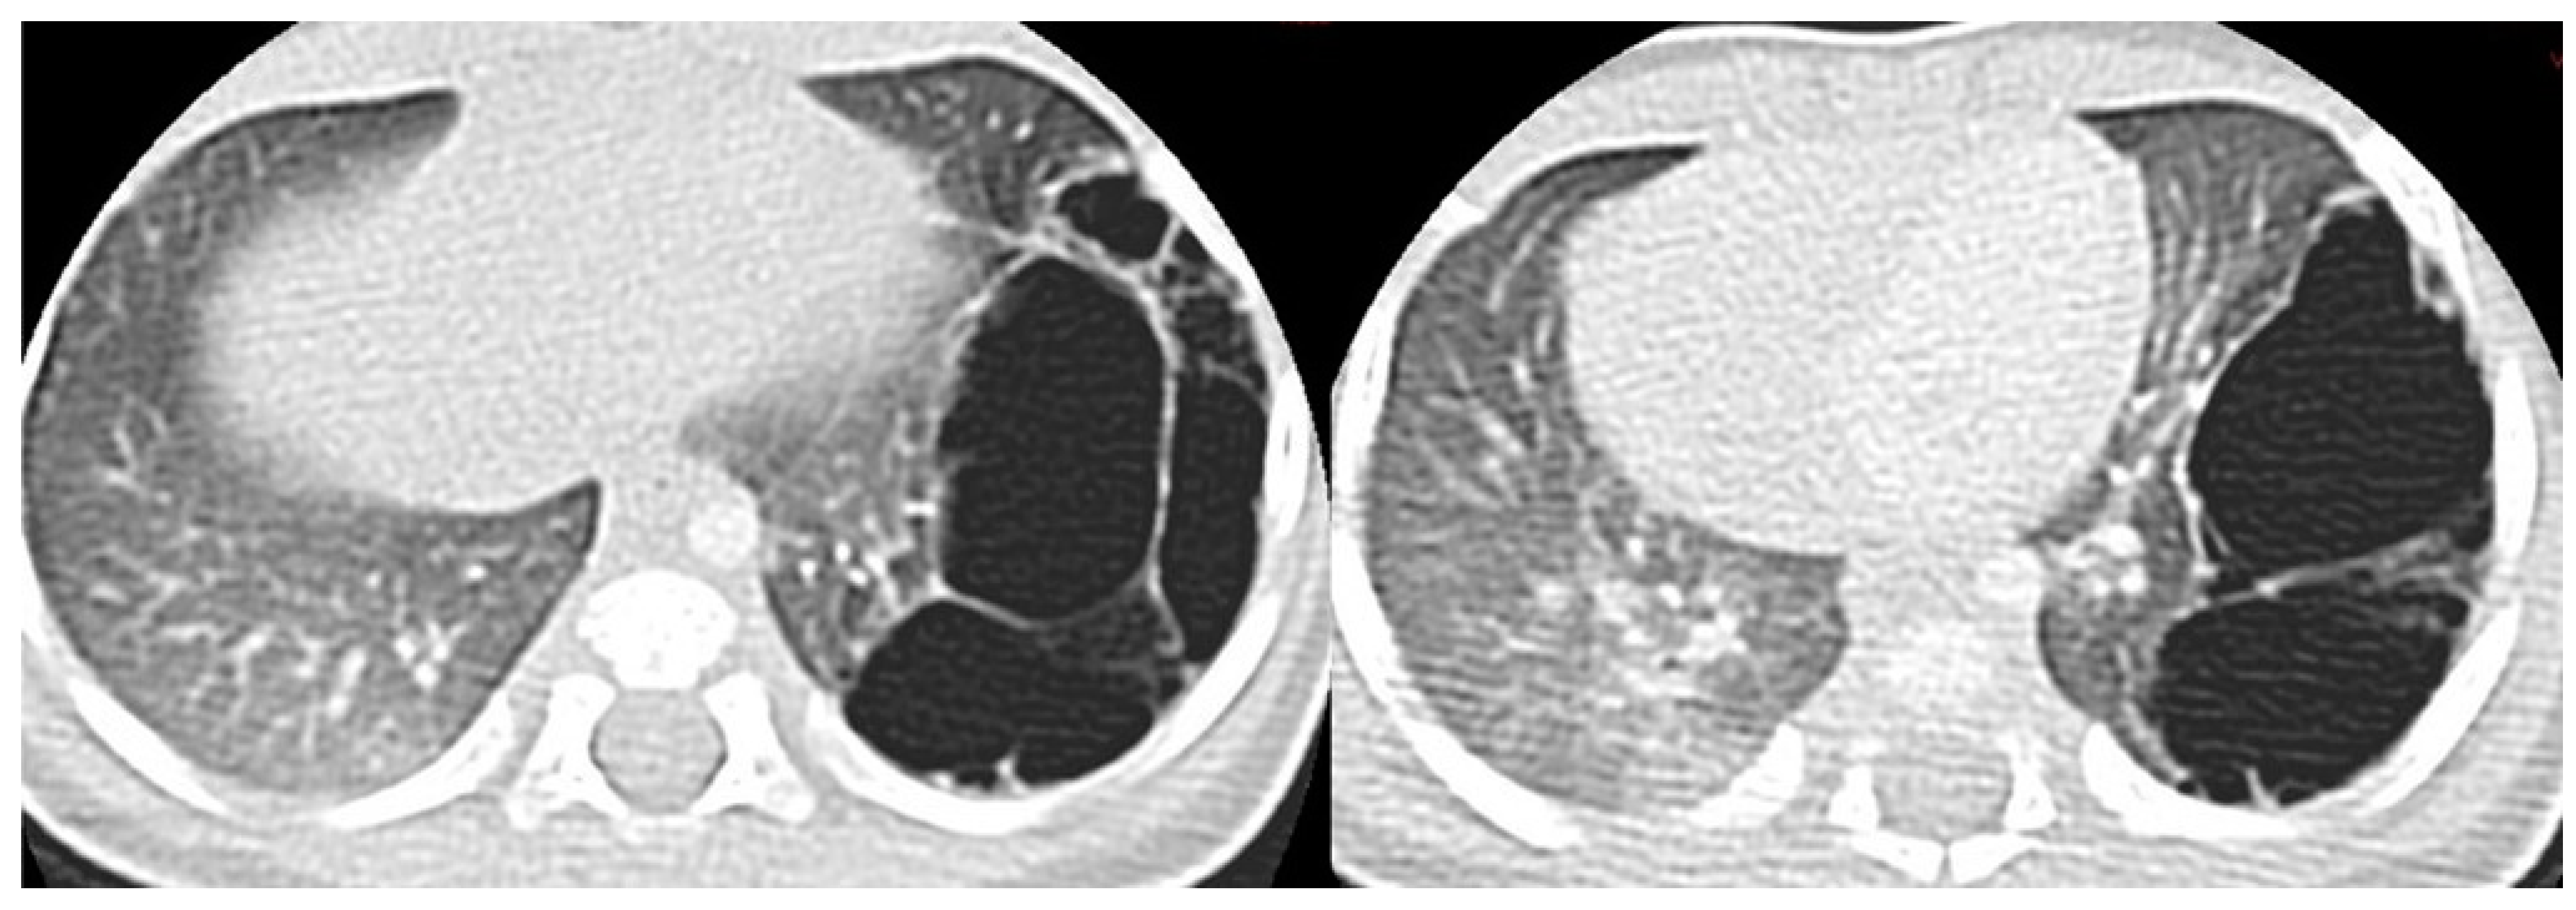

CT allows for the better evaluation of the lesion and its relationships with adjacent structures. On CT scans, lesions are detectable as well-defined air-filled spaces variable in size depending on CPAM type [15]: type 1 CPAM appears on CT as a one or multiple large cystic structures which can be entirely filled with air or with air-fluid levels (Figure 3, Figure 5 and Figure 6); type 2 CPAMs are visualized on CT as air-filled multicystic masses or focal or ill-defined areas of consolidation [3,15] (Figure 4 and Figure 7); type 3 typically exhibits a solid appearance on CT [15]. In infected CPAMs, imaging can demonstrate internal air-fluid levels and an enhanced thick wall.

Figure 5.

A CT scan performed one month later in the same patient as in Figure 3, showing multiple large air-filled cysts involving the left lower lobe, with a maximum diameter of 60 mm, confirming the diagnostic hypothesis of type 1 CPAM.